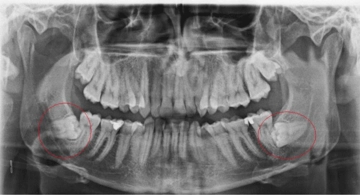

Diş hekimleri kök kalma riskini azaltmak için öncelikle detaylı radyografik incelemeler (panoramik röntgen, 3D tomografi) yaparak diş ve kök yapısını değerlendirir. Özellikle kırılgan, çürük veya şekli bozuk dişlerde dikkatli cerrahi teknikler uygularlar. Deneyimli hekimler, minimal travma prensibiyle çalışarak dişi bütün halinde çıkarmaya özen gösterirler.